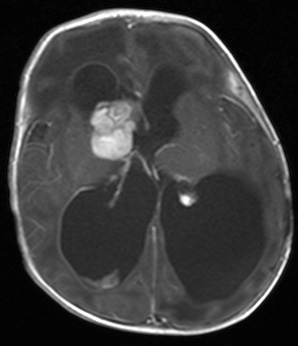

复查的头颅MRI检查提示孩子右侧脑室内占位性病变并交通性脑积水、间质性脑水肿,颅内硬膜下出血,增强扫描检查提示肿瘤病变均匀强化,肿瘤血供丰富(如下图)。